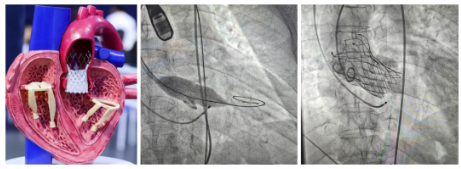

扬子晚报网12月11日讯(通讯员 刘柳 记者 万凌云 姜天圣)近日,镇江瑞康医院心血管内科在首席专家严金川教授的精心组织下,成功为一例重度主动脉瓣狭窄患者微创介入“换心门”。该技术称为经导管主动脉瓣植入术(TAVI)。

TAVI术中通过股动脉送入介入导管,首先采用球囊对患者重度狭窄的主动脉瓣膜进行预扩张,后将人工主动脉瓣膜送到拟释放位置,精确定位,人工瓣膜顺利释放,替换了原来重度狭窄伴钙化的瓣膜,术中经食道超声确认新的瓣膜位置准确、开放自如,患者主动脉瓣的功能得以恢复,手术成功。